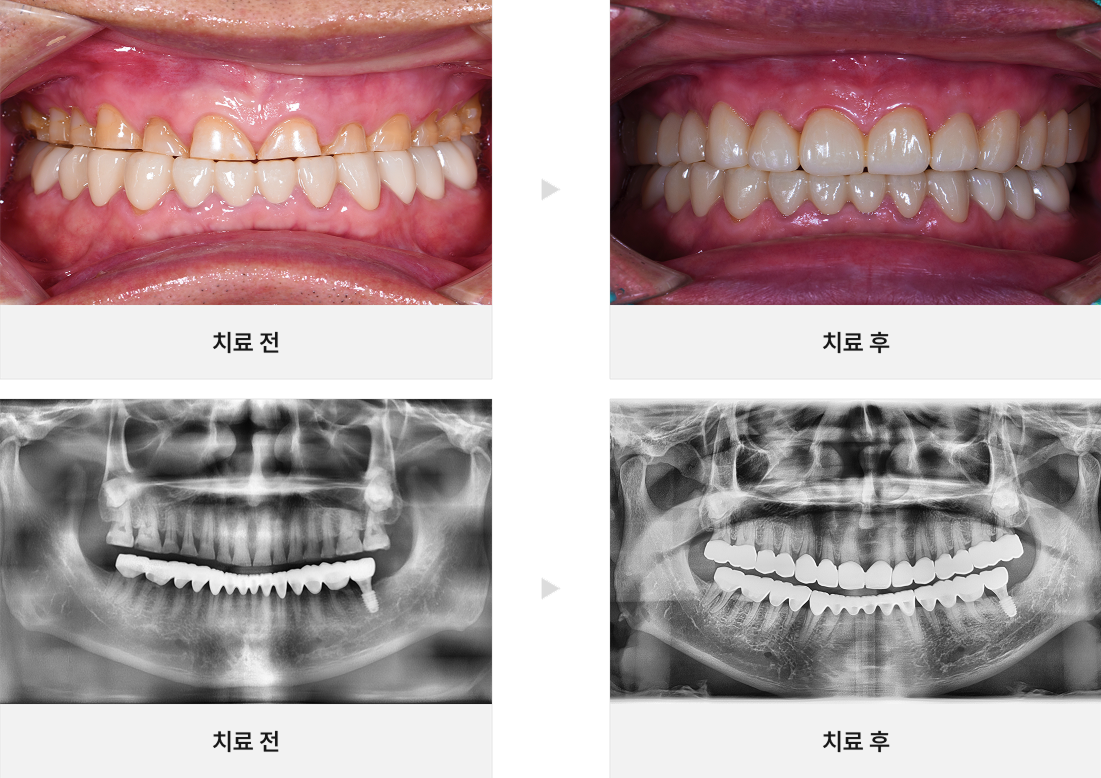

• CASE.03

뿌리 끝에 염증이 있는 치아 살리기

• CASE.04

충치가 있는 치아 살리기